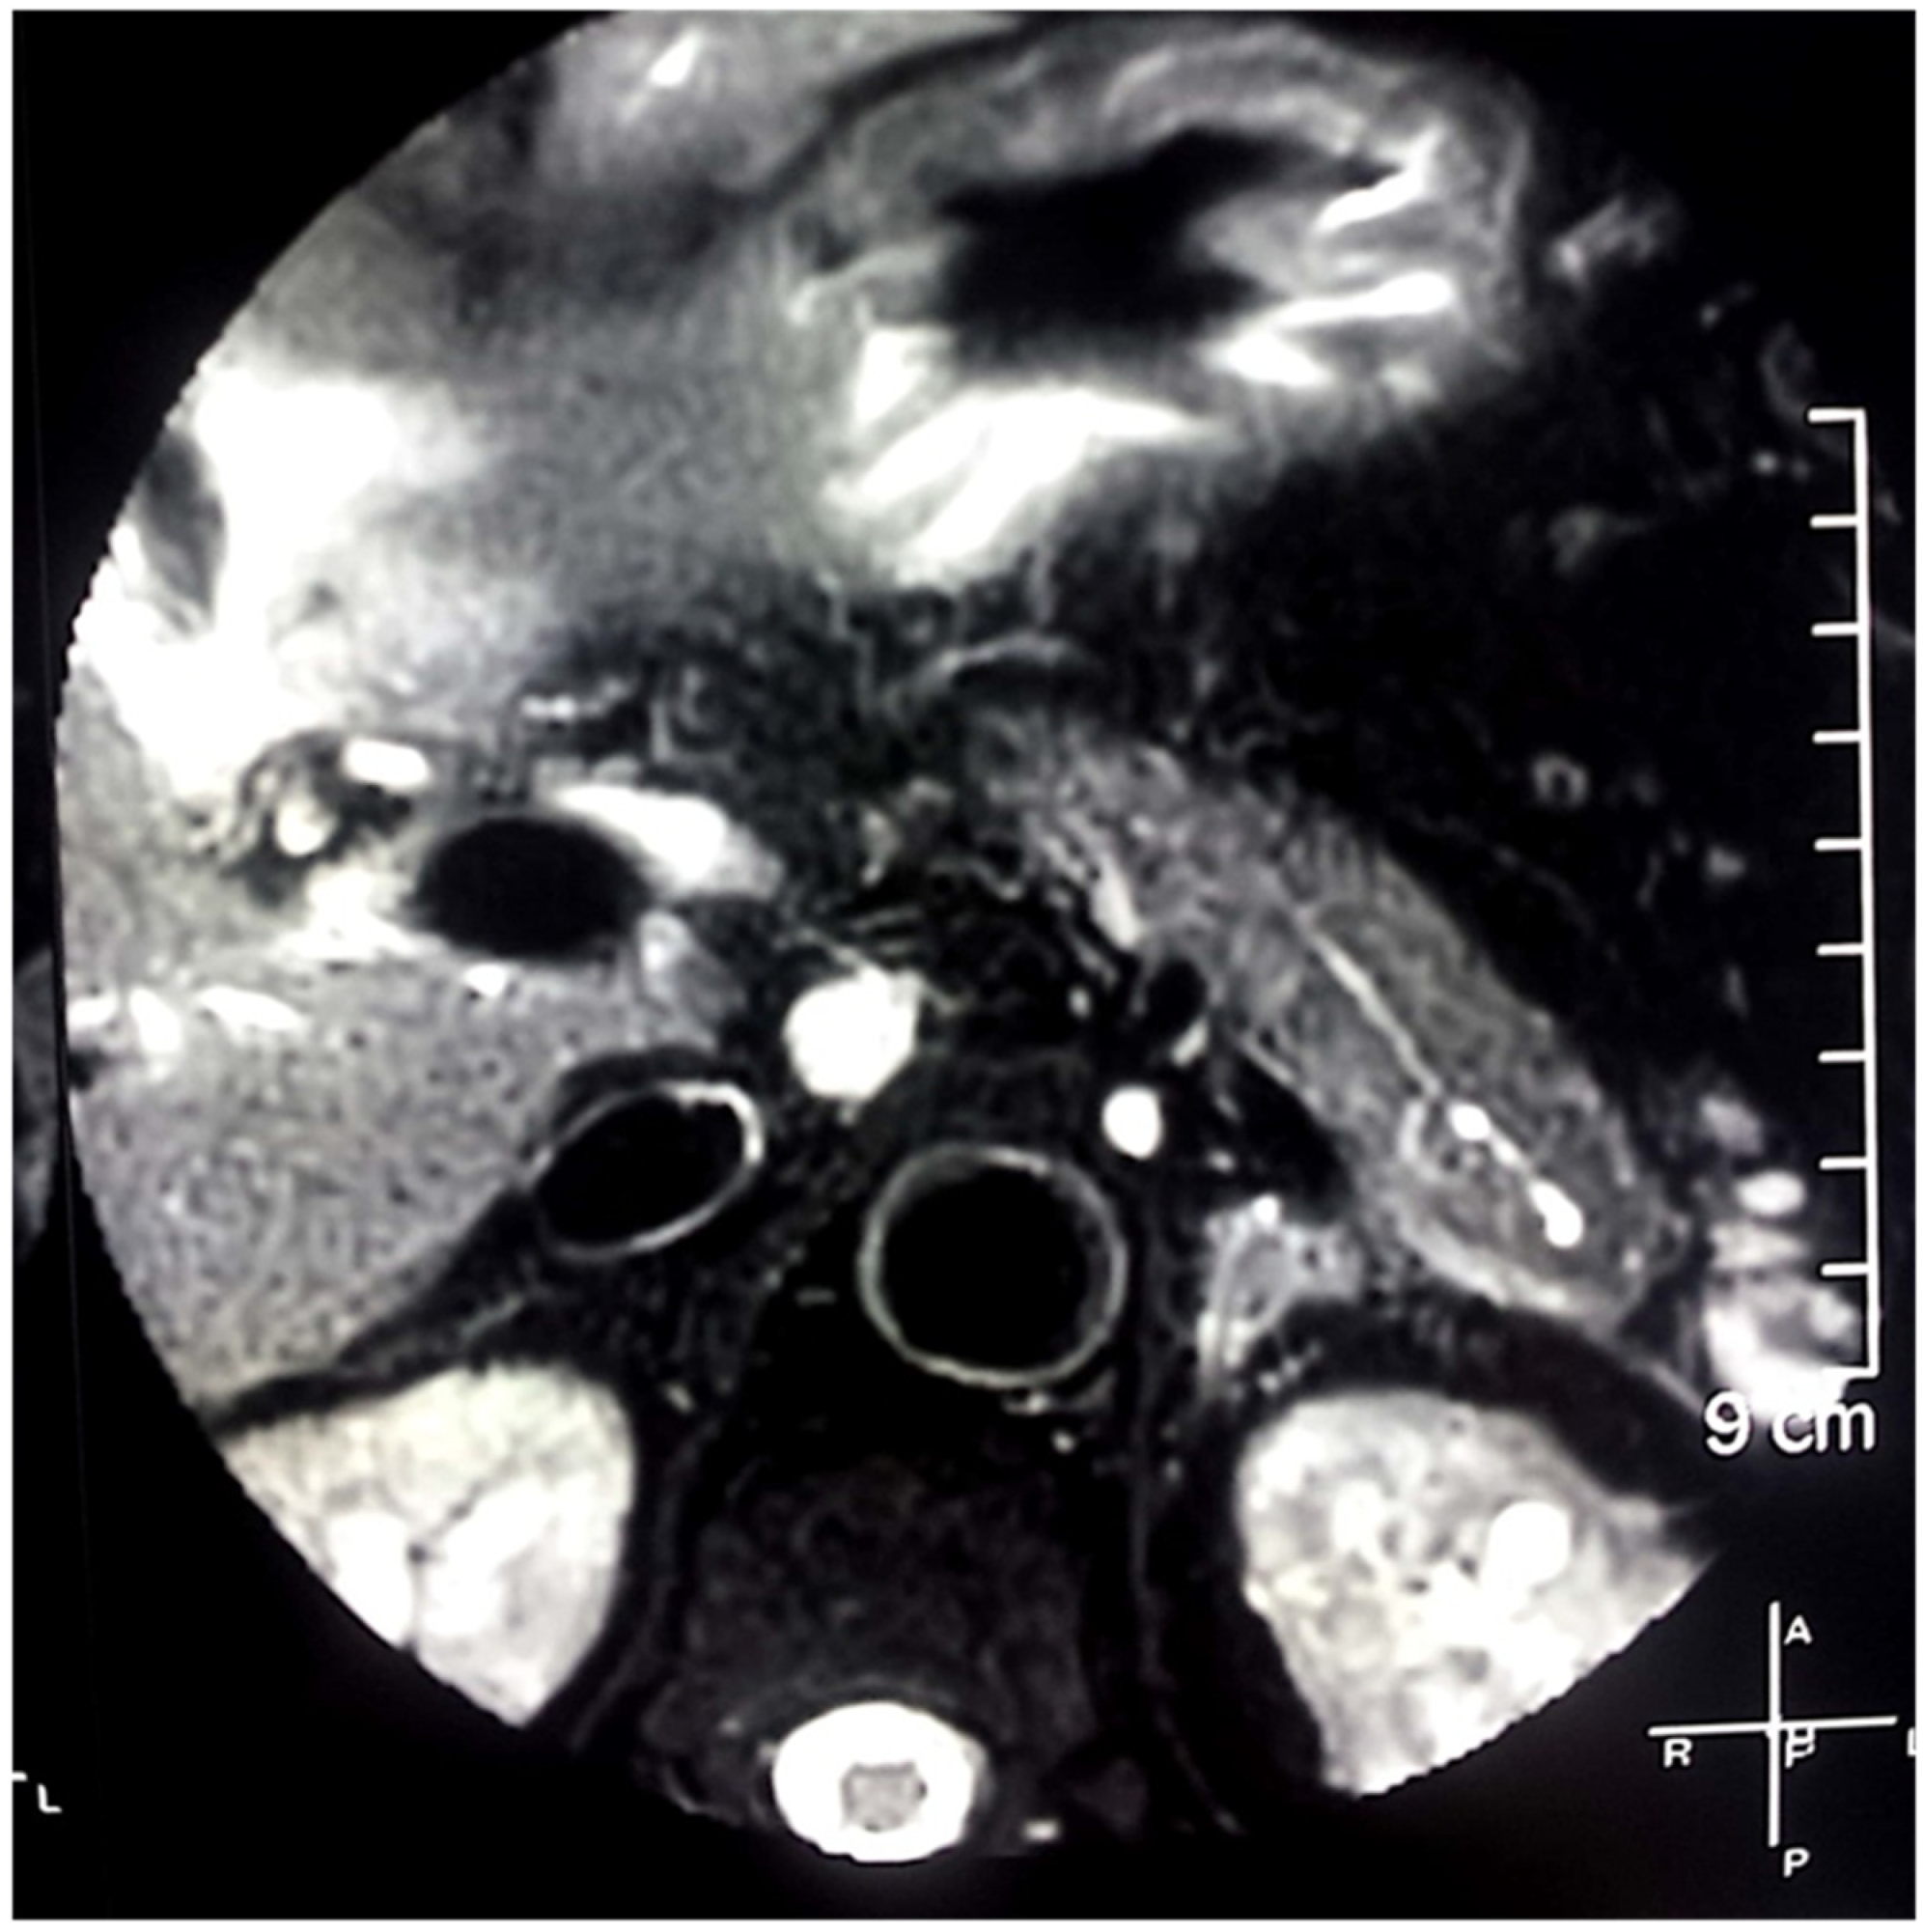

2. Case Report